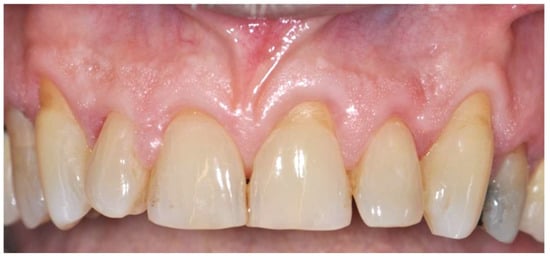

2. Case Presentation